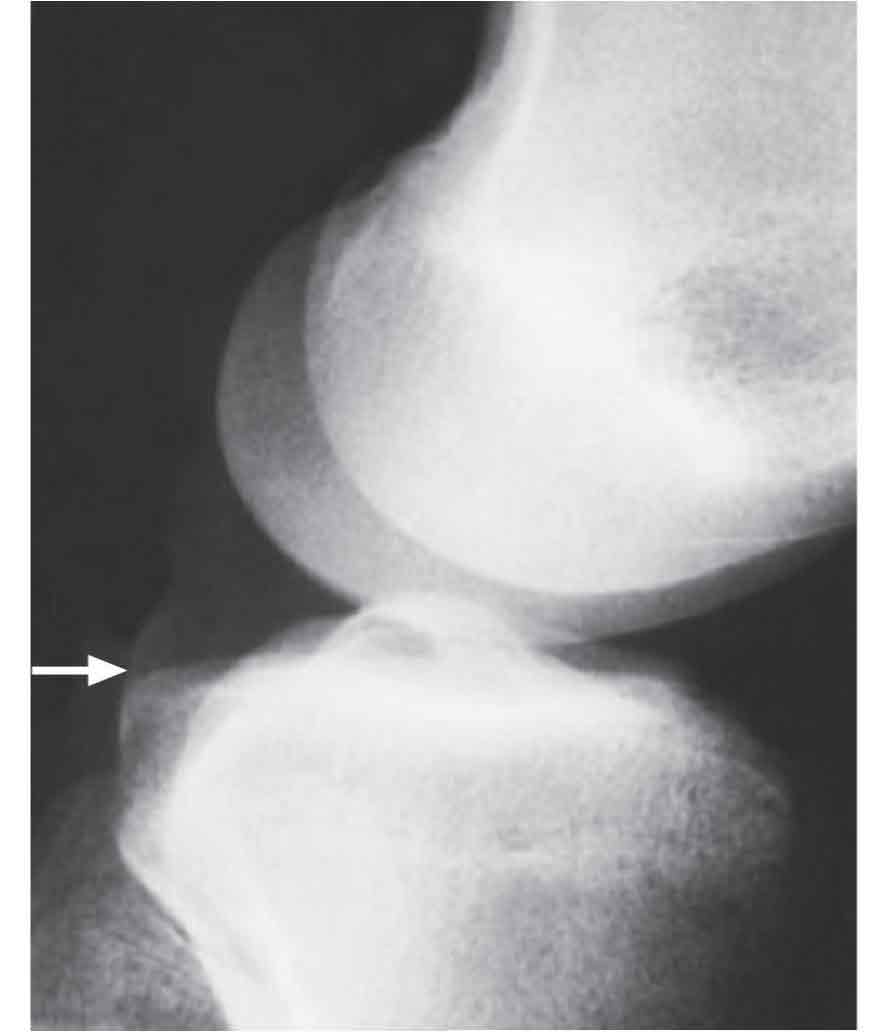

الفحوص الشعاعية: الصورة البسيطة مهمة جداً في تشخيص الكسور الانقلاعية للأربطة، وهي:

-1 كسر انقلاعي للارتكاز الفخذي للرباط الجانبي الإنسي.

-2 انقلاع مرتكز الرباط الجانبي الوحشي وأربطة المحفظة الخلفية الوحشية في كسر رأس الشظية الانقلاعي.

-3 كسر شوك الظنبوب الانقلاعي (كسر انقلاعي للمرتكز الظنبوبي للرباط المتصالب الأمامي).

-4 انقلاع الارتكاز الظنبوبي للرباط المتصالب الخلفي عن حافة الظنبوب الخلفية (الشكل24).

5- كسر الحافة القريبة من الطبق الظنبوبي الوحشي (انقلاع المرتكز العظمي للسبيل الحرقفي الظنبوبي) أو ما يسمى كسر سيغوند، وهو دليل على أذية رباطية وحشية شديدة ترافق أذية الأربطة المتصالبة، وقد تكون الدليل الوحيد على حدوث خلع ركبة رضي ارتد تلقائياً (الشكل25).

الشكل (25) كسر سيغوند